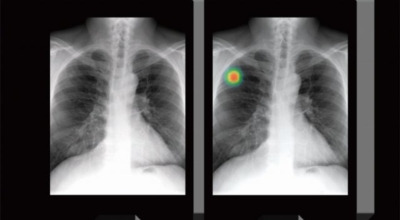

폐암 검사는 주로 X-ray를 통해 이루어지지만, 종양의 크기가 작거나 구석에 위치한 경우에는 확인이 어려운 경우도 있습니다. 그 후, 조직 검사를 통해 정확한 진단을 하게 됩니다. 폐암이 발견되면, 종양의 크기, 전이 여부, 위치에 따라 수술 여부를 결정하게 됩니다.